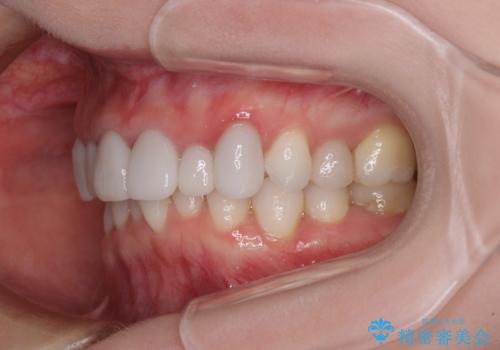

- 全体的なデコボコと、奥歯の欠損を放置した結果倒れ込んだ奥歯などを気にして来院された患者様です。

ワイヤー矯正の方が理想的な仕上がりとできる状態でしたが、上顎前歯にクラウンが装着されているため、インビザラインにて矯正治療を行うこととしました。

インビザラインのみで対応できないときにはワイヤー矯正を併用することとし、矯正治療後にはオールセラミッククラウンによる補綴治療を行うこととしました。

矯正治療自体はインビザラインで満足のいく仕上がりとなりました。

前歯は根管治療が必要となり、元々舌側に入り込んでいた左上2番目の歯は歯周外科処置により歯肉ラインを整えることとしました。

欠損部位は傾斜歯軸を起き上がらせることができたため、オールセラミッククブリッジにて補綴治療を行いました。

全顎的に満足のいく仕上がりとなりました。